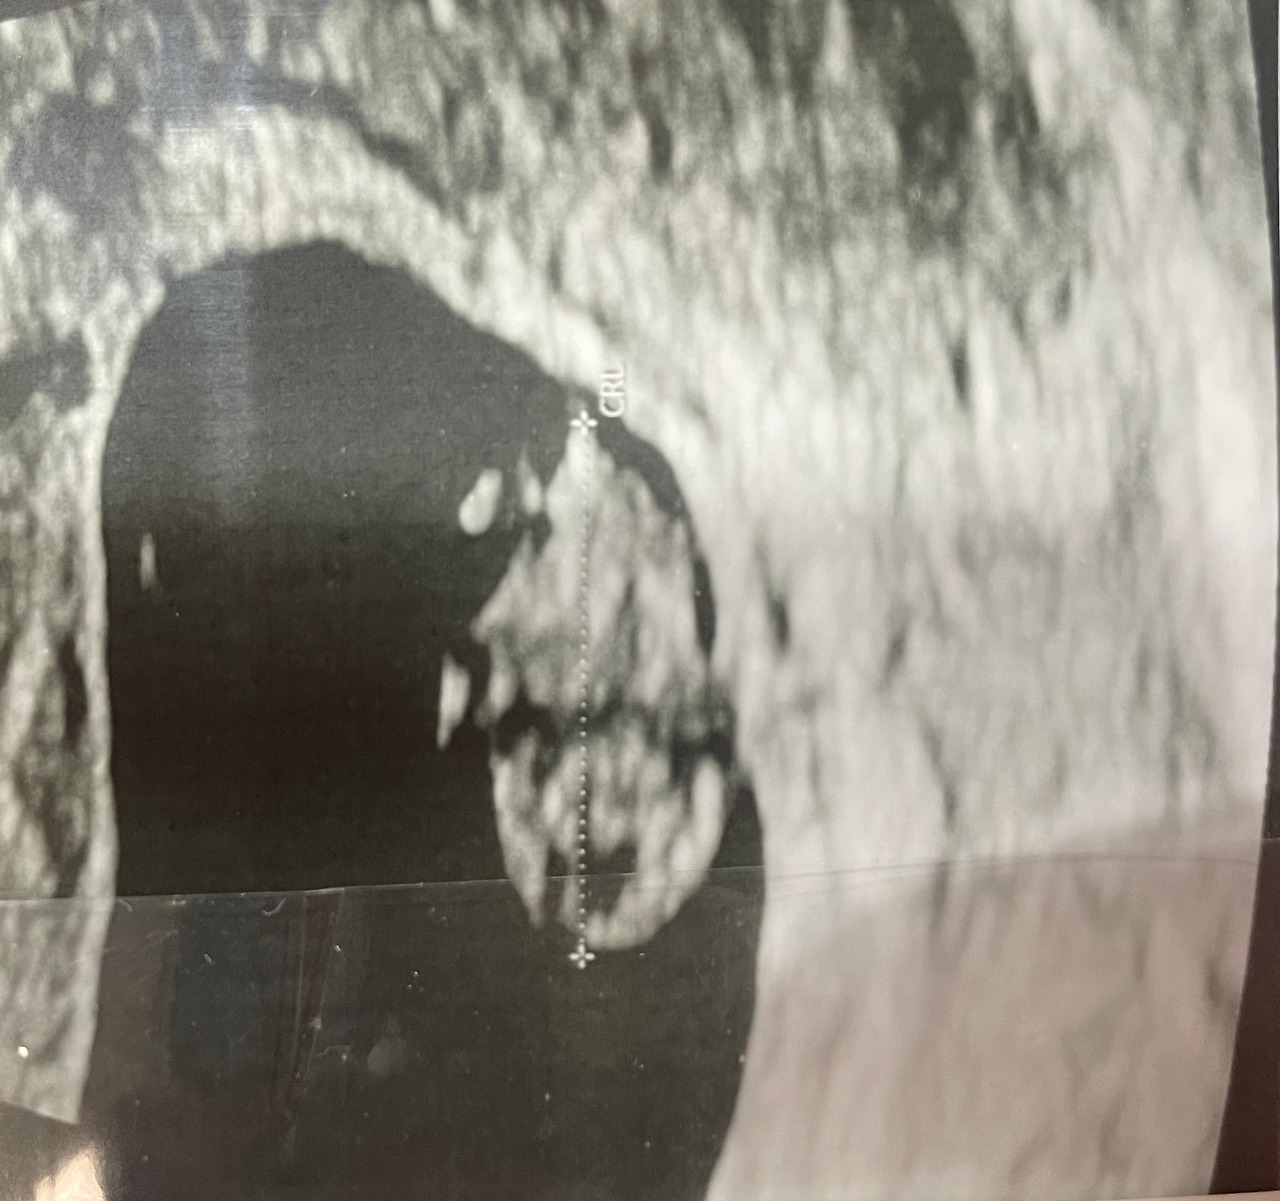

8주 2일

어수선한 진료 대기실도 조금은 익숙해졌고, 아내의 이름이 불리며 쿵쾅거렸던 나의 심장도 이제는 제법 편안함을 찾았다. 그리고 아주 작은 아이는 우리에게 열심히 손을 흔들어 주었다.

심장은 어찌나 빨리 뛰는지 방안에 아이의 두근거림이 가득찰 정도였다.

비록 하리보의 형태는 아니었지만, 저 조그마한 팔과 다리가 벌써부터 소중하다.